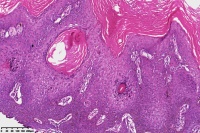

脂溢性角化症伴皮角?

女

年龄

49岁

手臂皮肤组织

图1

脂溢性角化病